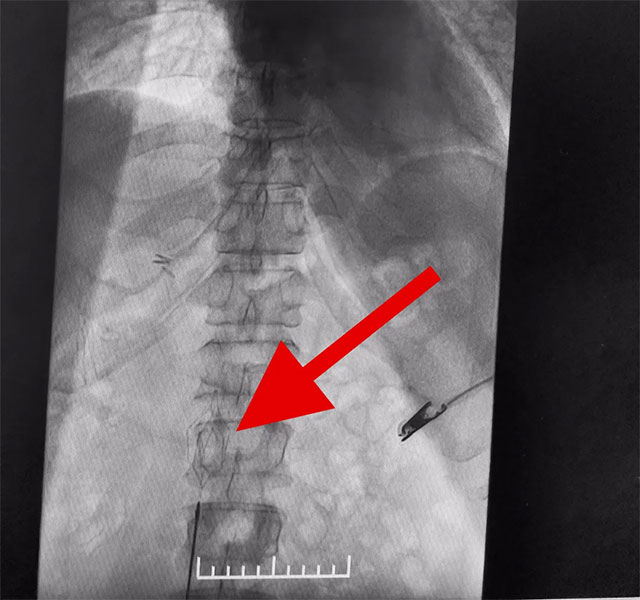

在征得家属同意后,6月12日,张琪博士团队为患者进行了下腔静脉滤器置入手术。张琪博士在医护团队协助下将一个形似伞状的人工滤器经患者右侧股静脉穿刺迅速置入下腔静脉,“网”住了通往心血管和肺部的致命栓子,阻挡血液栓子进入肺动脉,及时挽救了患者生命。

▲ 下腔静脉滤器置入成功

下腔静脉滤器置入是为了预防下腔静脉系统栓子脱落引起肺栓塞而设计的一种装置,分为永久性和可回收两种。可回收滤器可经健侧股静脉、亦可经颈内静脉置入。该手术通过滤器输送器,将滤器在X线透视下送入,确定位置无误后,后撤输送器直至滤器弹开、释放。